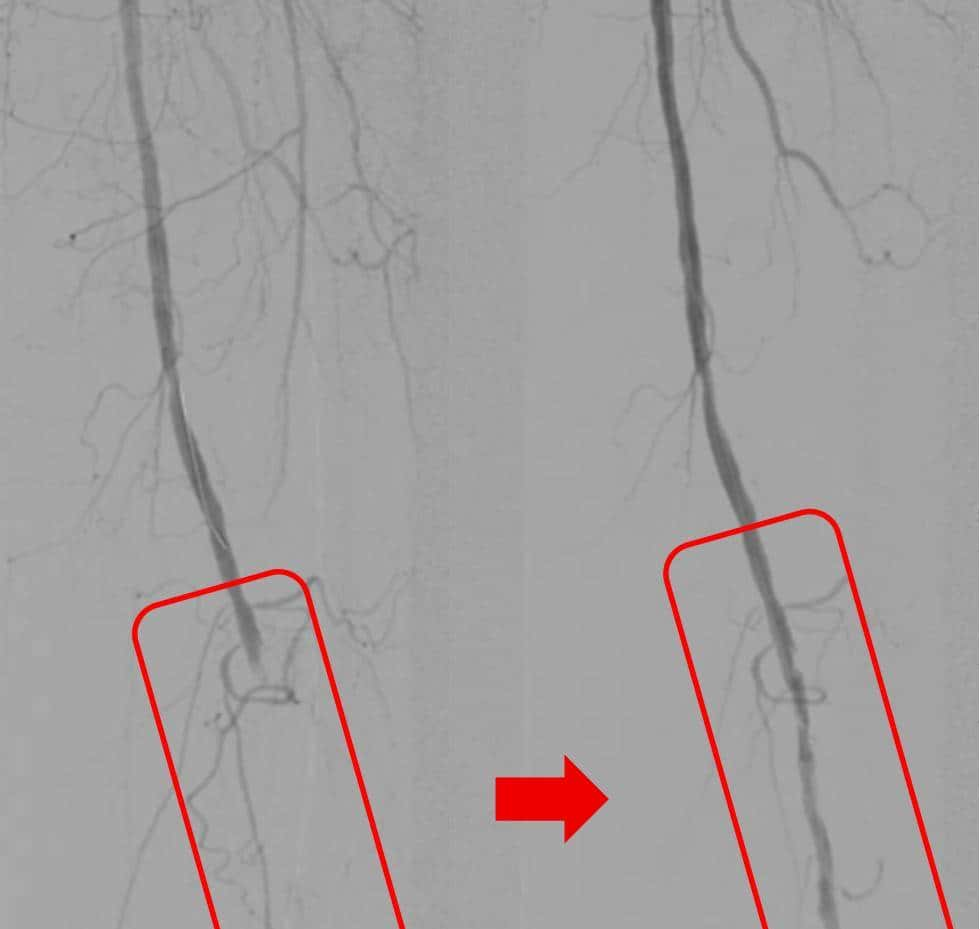

红框内的下肢动脉血栓被清除